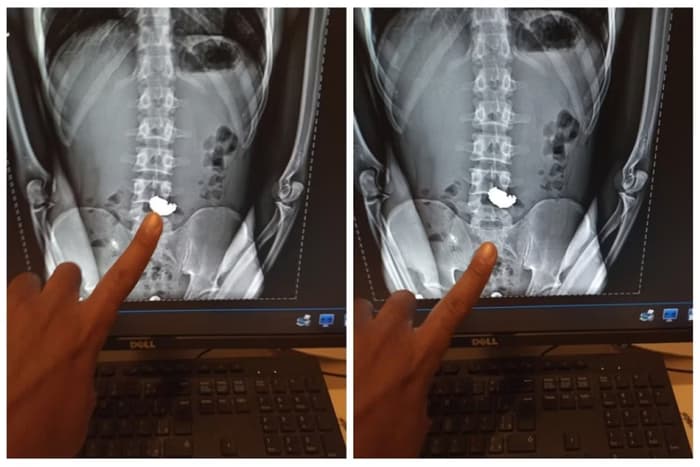

No hospital, o homem passou por uma radiografia que constatou a presença do acessório de ouro no estômago do suspeito.